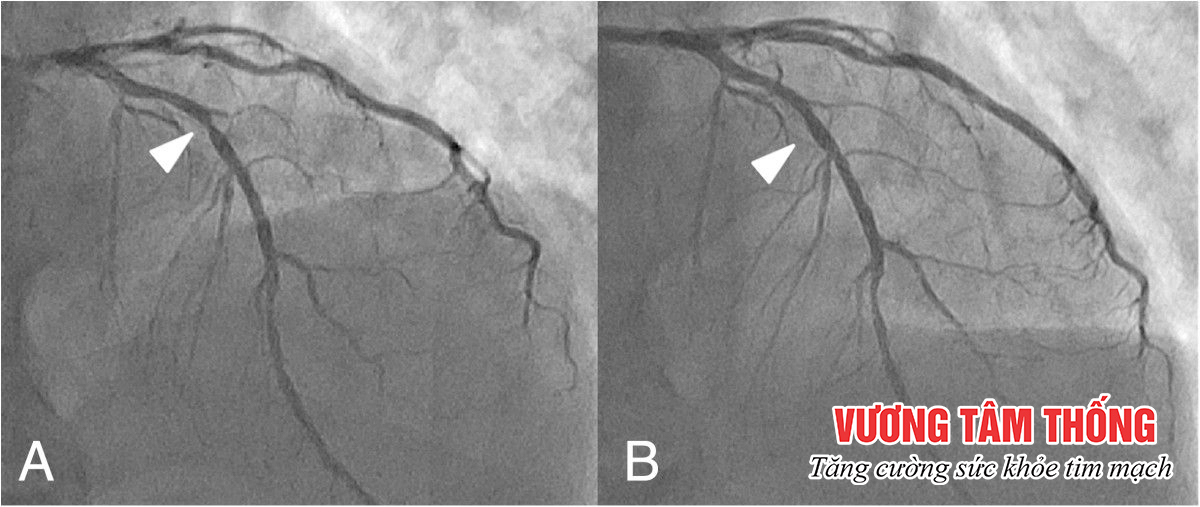

Sự ra đời của stent mạch vành giúp làm giảm đáng kể số ca tử vong do nhồi máu cơ tim hay hẹp mạch vành nặng. Tuy nhiên, đứng trước nguy cơ phải tiến hành can thiệp xâm lấn nhiều người bệnh vẫn lo